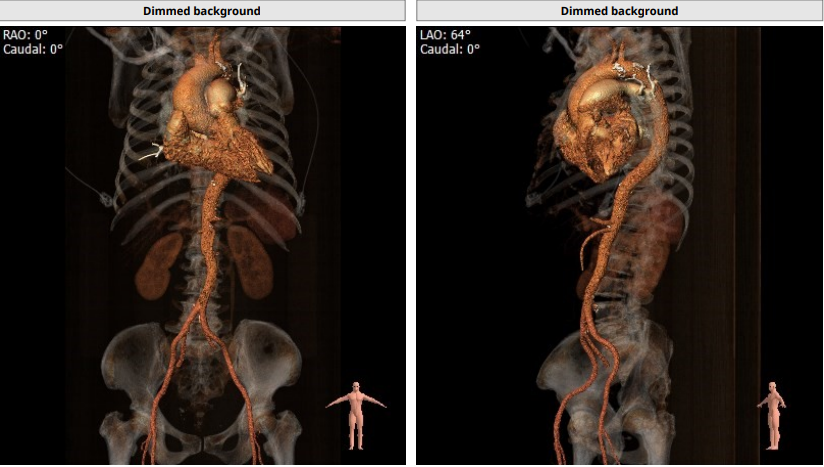

CT报告评估:

Annulus:24.4mm,LVOT:22.6mm,Asc.Ao:43.4mm,STJ:30.7mm。

LCA:10.7mm,RCA:15.0mm。

瓣环结构及钙化情况:患者为TYPE 1型二叶瓣,瓣环及左室流出道呈上宽下窄型结构,钙化积分为529,主要集中于无冠窦,从基底部开始延申至左右融合处及无冠窦游离缘,整体窦部空间合适。

心室情况:升主动脉增宽,心脏角度59°,严重心肌增厚,心室腔小。

入路情况:主动脉弓部有斑块附着,髂总动脉少许斑块附着。